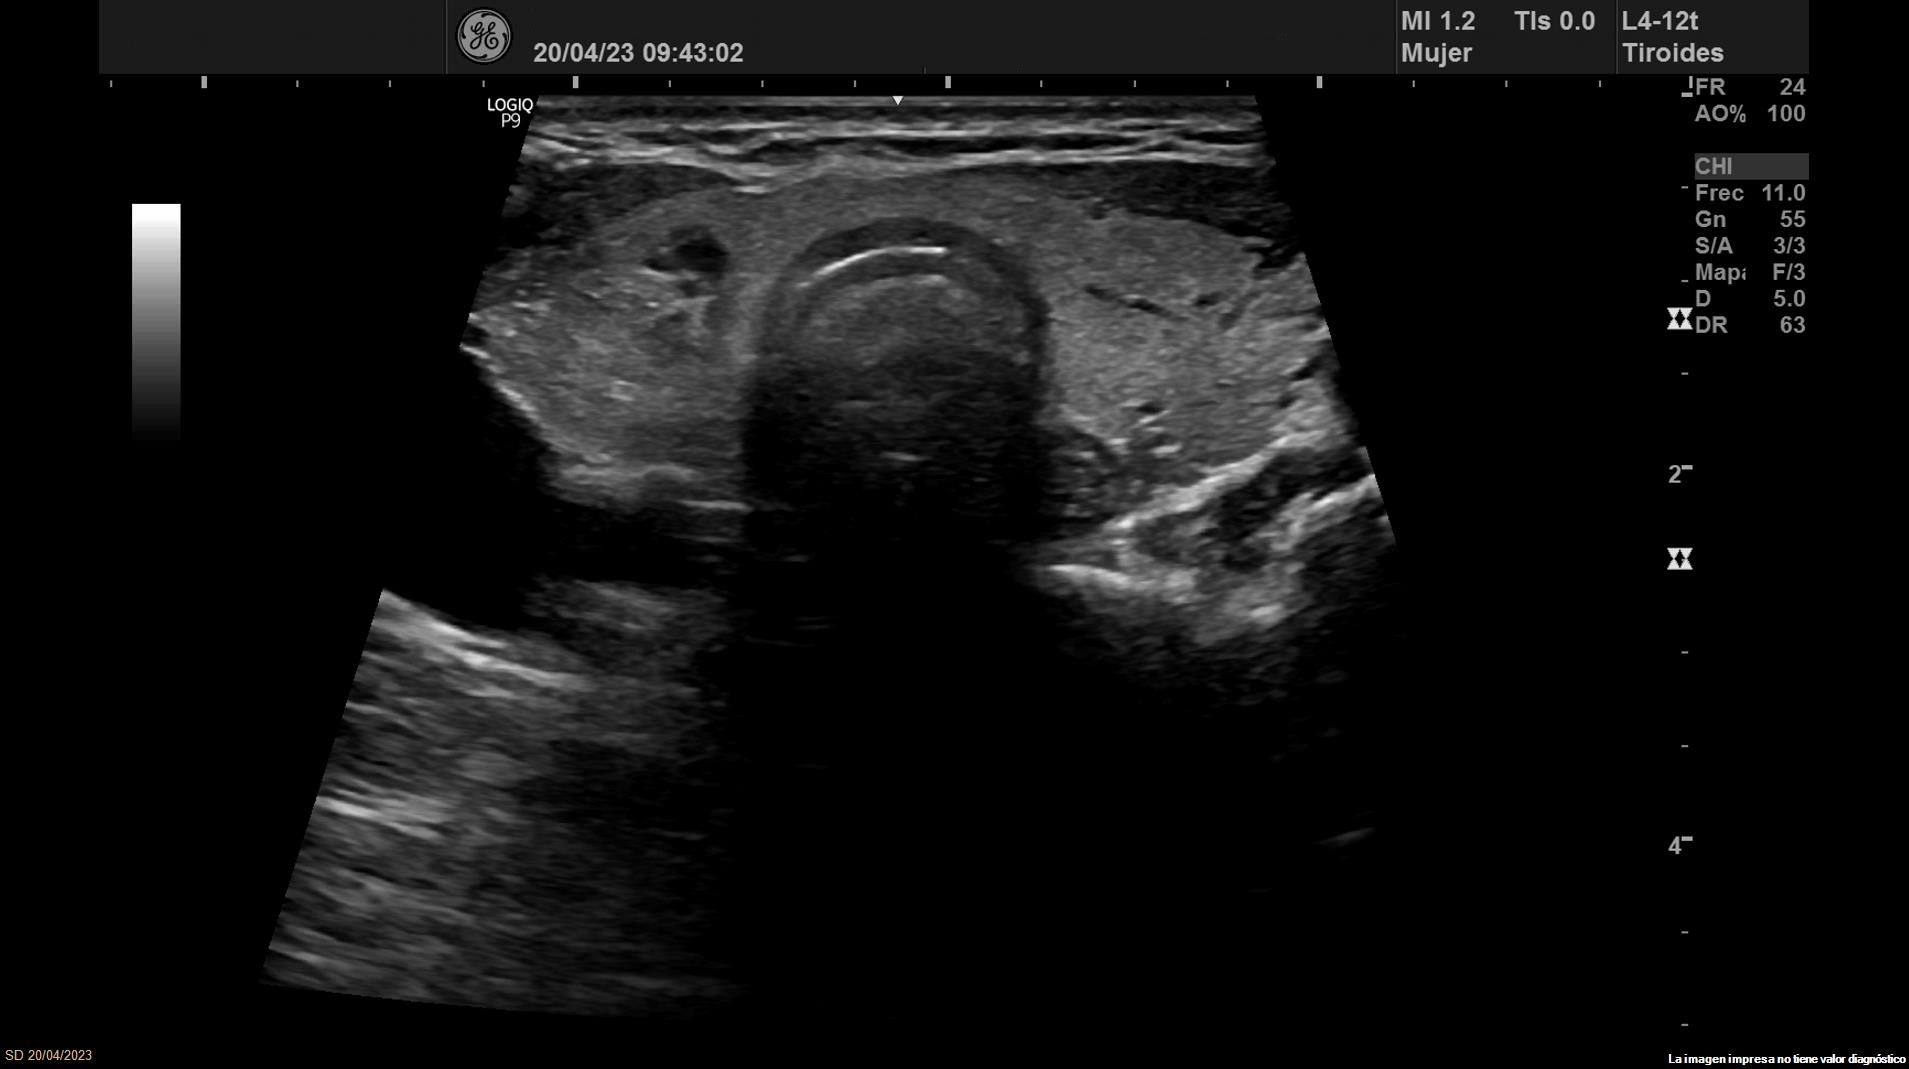

Se objetiva una adenopatía de 0,8 cm de aspecto benigno, ovalada y con bordes definidos. Además, se realiza ecografía tiroidea:

• Lóbulo tiroideo derecho: tamaño normal. En tercio inferior nódulo único espongiforme con área quística inferior que mide 15 mm de diámetro mayor longitudinal (ATA: baja sospecha).